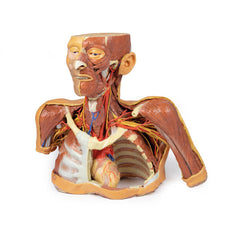

3D Printed Sagittal Section of Head with Infratemporal Fossa Dissection

3D Printed Sagittal Section of Head with Infratemporal Fossa Dissection

This 3D model provides a combined midsagittal section through the head and

superior neck coupled with a deep dissection into the infratemporal fossa

region and superficial dissection of the scalp.

The deep level of dissection has exposed parts of the infratemporal fossa

(through partial removal of the mandibular ramus and corpus) and dissection

of retromandibular tissues. At the inferior margin of the dissection window,

the cut edge of the retromandibular vein lies adjacent to the submandibular

gland and the ascending path of the facial artery as it cross towards to angle

of the mouth. Just superior to the cut retromandibular vein is the posterior

belly of the digastric muscle, overlying a small exposure of the deeper

internal jugular vein.

Just posterior to the retained ascending ramus of the mandible are the

external carotid artery and the occipital artery (running in parallel prior

to passing posteriorly). Tracing the external carotid artery superiorly, the

posterior auricular artery, superficial temporal artery, and maxillary artery are

all visible. The maxillary artery passes deep to the lateral pterygoid muscle

and into the infratemporal fossa, reappearing superior to the lateral pterygoid

as it passes into the pterygomaxillary fissure. Along its course, it gives rise

to the posterior deep temporal artery, the inferior alveolar artery (which is

exposed in the dissected mandibular corpus), the anterior deep temporal

artery, and the posterior superior alveolar artery. Finally, the inferior alveolar

nerve can be seen coursing within the opened mandibular corpus, and the

lingual nerve resting on the medial pterygoid. The buccinator muscle is also

retained, with the distal part of the parotid duct preserved as it enters the

muscle towards the oral mucosa